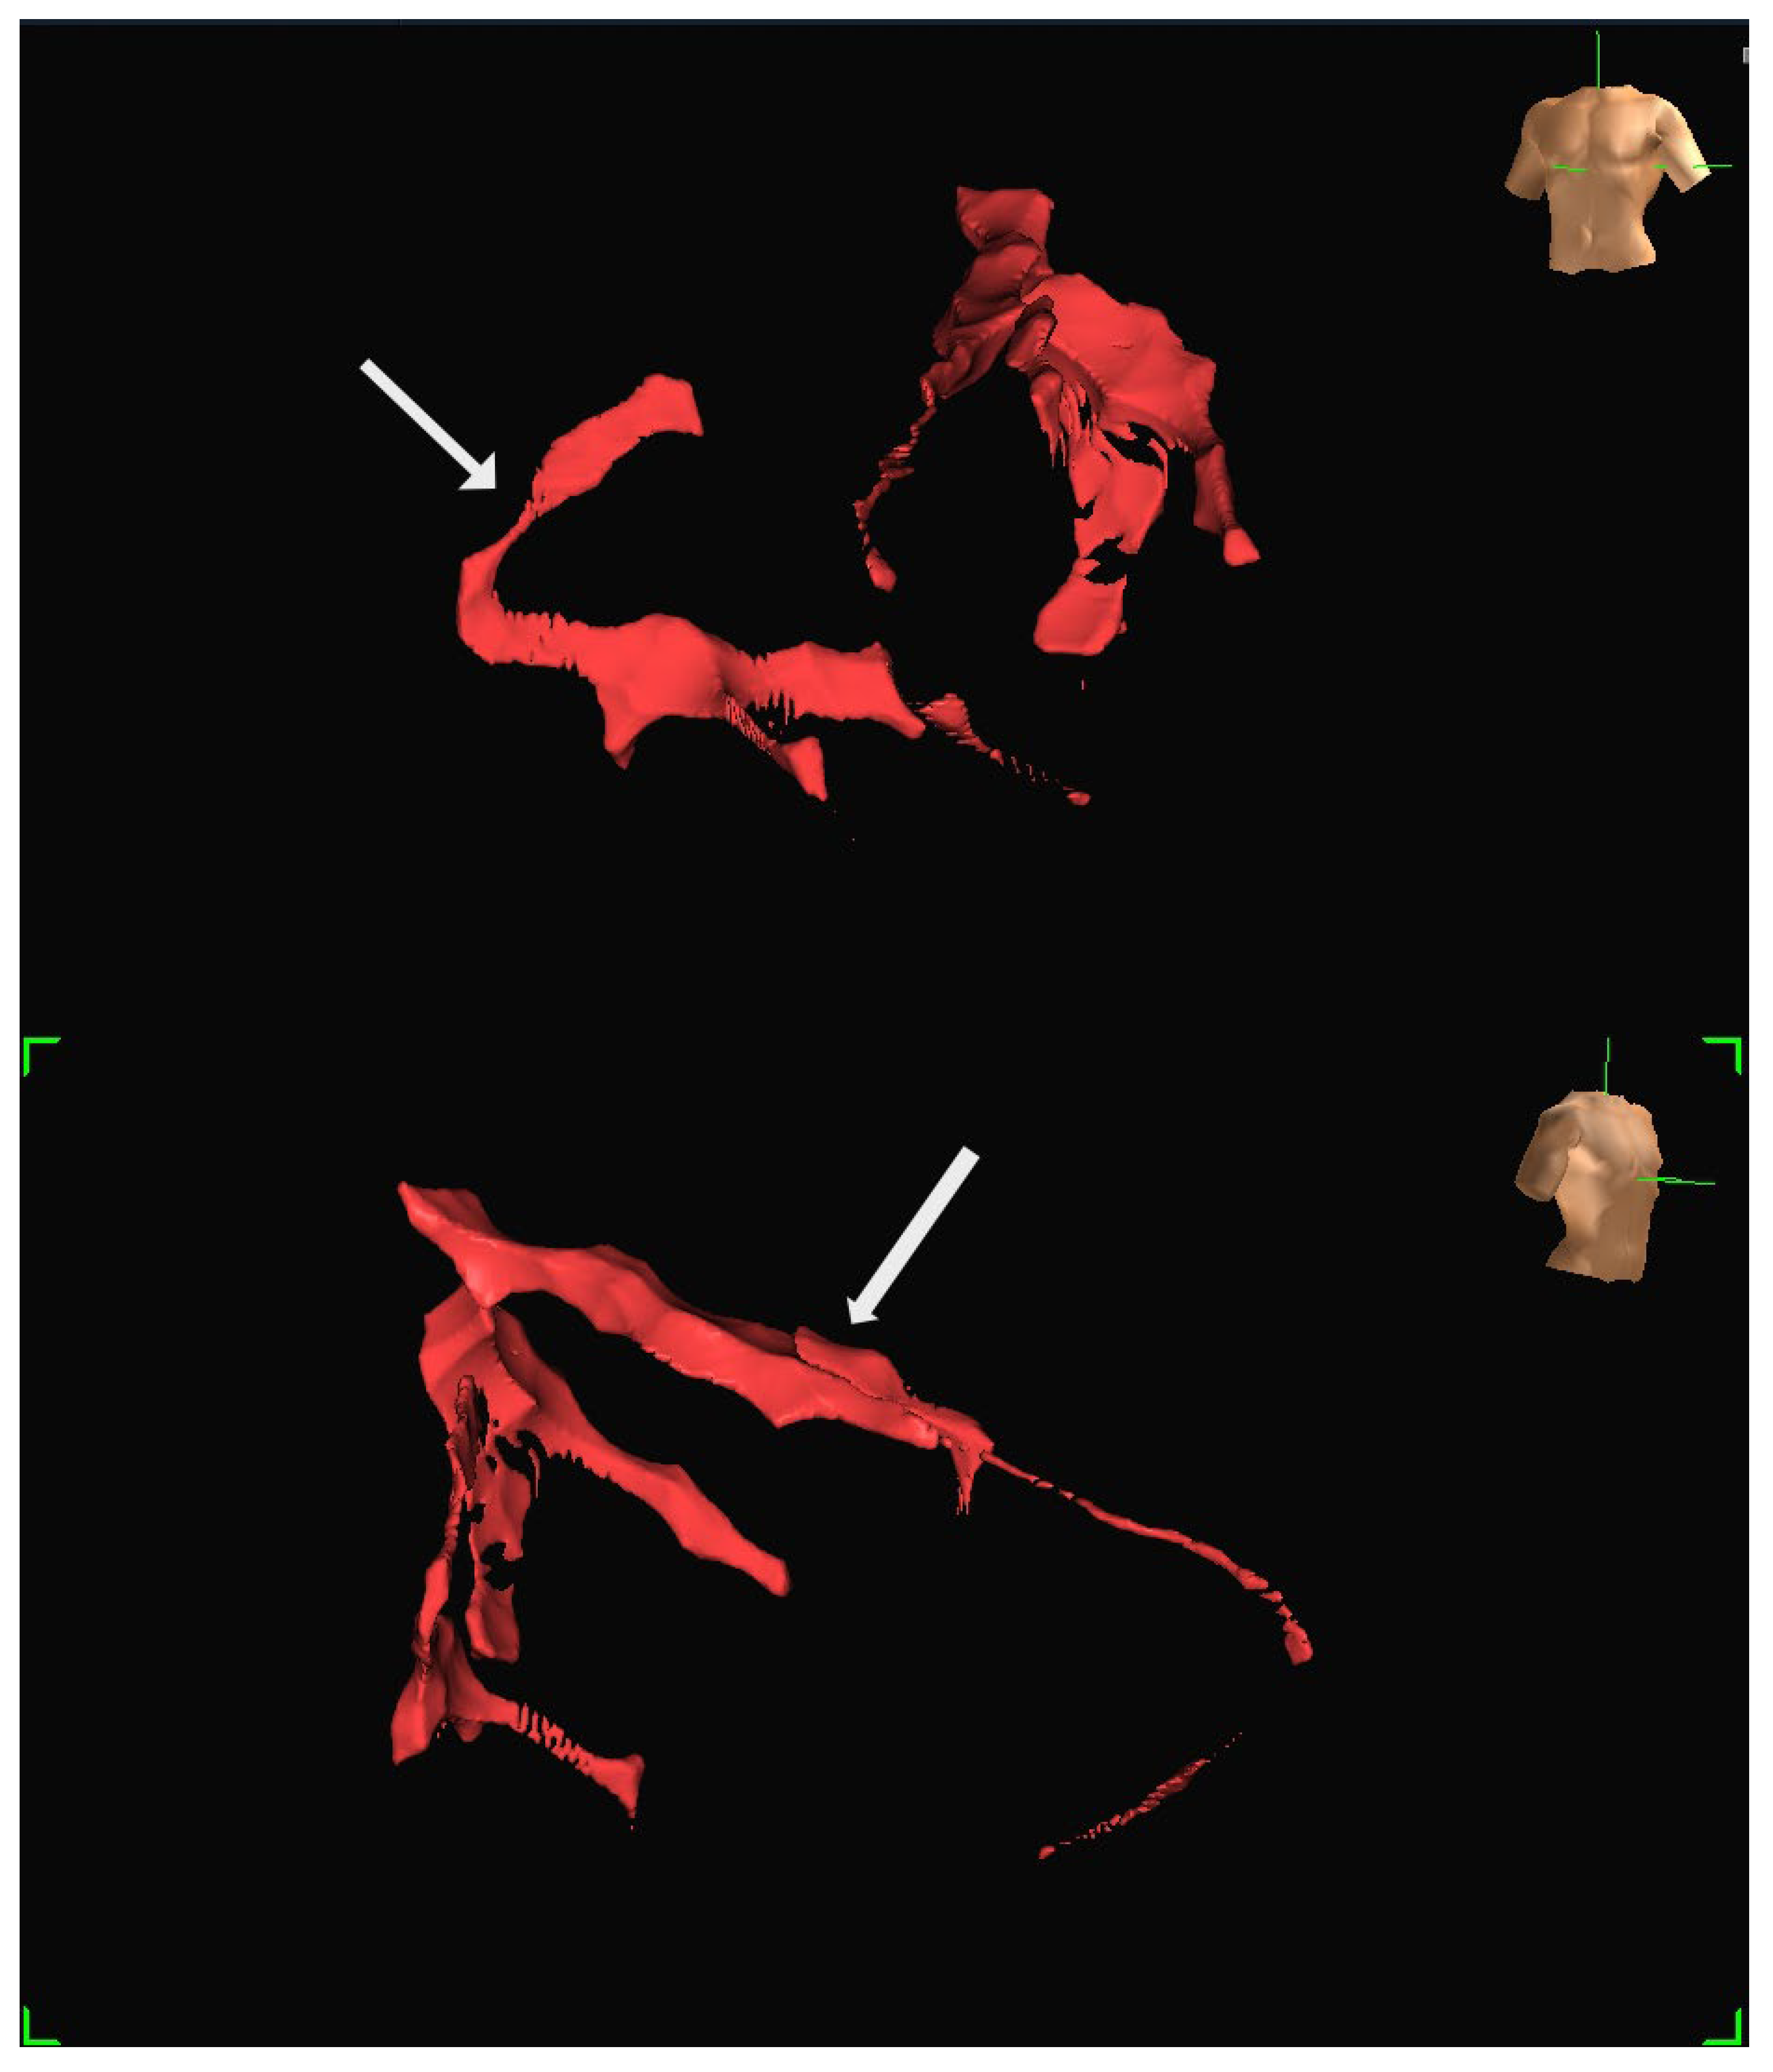

A human feasibility study involving multiple participants was conducted using the EnSite Precision system [13]. Insulated Sion Blue coronary guidewires (Asahi Intec, Japan) were tracked through epicardial arteries, including the left anterior descending and right coronary arteries, to produce anatomical reconstructions closely matching conventional angiographic images. The mapping system tracked the distal wire tip based on impedance field localisation. System accuracy was further evaluated in a custom-built water bath model incorporating segmented CT data. In this controlled setup, bipolar catheters fabricated from over-the-wire balloons and coronary wires were advanced through fixed vessel phantoms, confirming consistent localisation and map generation. Representative three-dimensional reconstructions generated using the EnSite Precision mapping system are shown in Figure 4 and Figure 5. These panels depict different views from the same patient, illustrating how coronary anatomy was mapped and visualised during the feasibility study.

Figure 4. Representative three-dimensional reconstruction of coronary anatomy generated using the EnSite Precision EAMS. The geometry was derived from guidewire tracking in a single patient. The coronary vessels are displayed in red: (Top) Left anterior oblique (LAO) projection, with the RCA marked by an arrow. (Bottom) Right anterior oblique projection (RAO), with LAD marked by an arrow. Torso icons indicate image orientation.

Figure 5. Additional views of the same patient dataset shown in Figure 4, demonstrating the ability to visualise the vessel course from different angles: (Top) The LAD is marked by an arrow. (Bottom) RCA is marked by an arrow. Both images are displayed in LAO projection at different angulations.